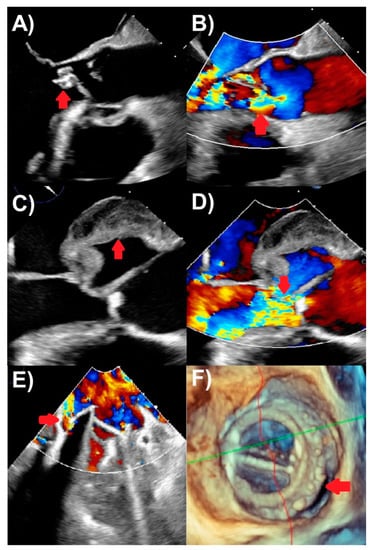

3.3. Three-Dimensional Echocardiography

- Pérez-García, C.N.; Olmos, C.; Islas, F.; Marcos-Alberca, P.; Pozo, E.; Ferrera, C.; García-Arribas, D.; De Isla, L.P.; Vilacosta, I. Morphological characterization of vegetation by real-time three-dimensional transesophageal echocardiography in infective endocarditis: Prognostic impact. Echocardiography 2019, 36, 742–751. [Google Scholar] [CrossRef] [PubMed]

- García-Fernández, M.A.; Cortés, M.; García-Robles, J.A.; de Diego, J.J.G.; Perez-David, E.; García, E. Utility of real-time three-dimensional transesophageal echocardiography in evaluating the success of percutaneous transcatheter closure of mitral paravalvular leaks. J. Am. Soc. Echocardiogr. 2010, 23, 26–32. [Google Scholar] [CrossRef]

- Berdejo, J.; Shibayama, K.; Harada, K.; Tanaka, J.; Mihara, H.; Gurudevan, S.V.; Siegel, R.J.; Shiota, T. Evaluation of vegetation size and its relationship with embolism in infective endocarditis: A real-time 3-dimensional transesophageal echocardiography study. Circ. Cardiovasc. Imaging 2014, 7, 149–154. [Google Scholar] [CrossRef]